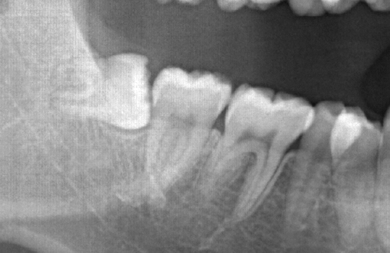

| 治療方針 | 歯のがたつきが大きいことより上下左右第一小臼歯を抜歯して、マルチブラケット装置にて治療。また、親不知がまっすぐ生えることができず横を向いている状態なので、まっすぐにする隙間があることから親不知も使用し、矯正を行う。 | ||||||||||||||||||||||||||||||||